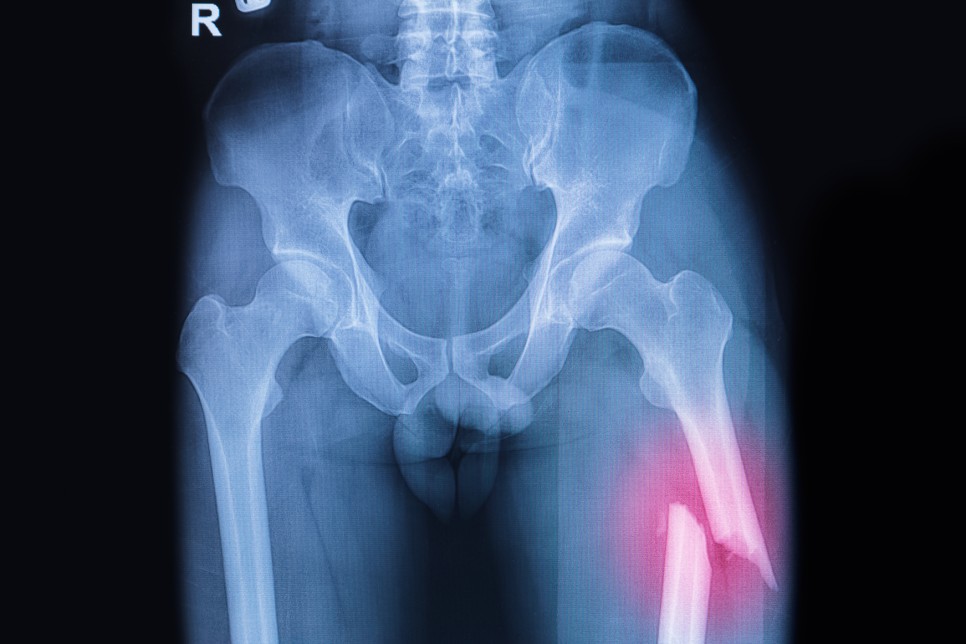

- 골절치료 및 뼈관련 질환 치료

- 홍화씨는 칼슘이 풍부하여 뼈를 튼튼하게 합니다슬통, 관절염, 요통 등의 관절과 골질환 치료에 도움이 됩니다.또한 골절되었을 때 뼈가 붙도록 돕는 물질의 분비를 촉진하여 뼈의 재생과 회복을 돕습니다.특히 풍부한 칼슘은 갱년기 여성의 골다공증 완화에도 도움을 주며 성장기 어린이에게도 골격을 튼튼하게 성장시키는 필수 영양분입니다.